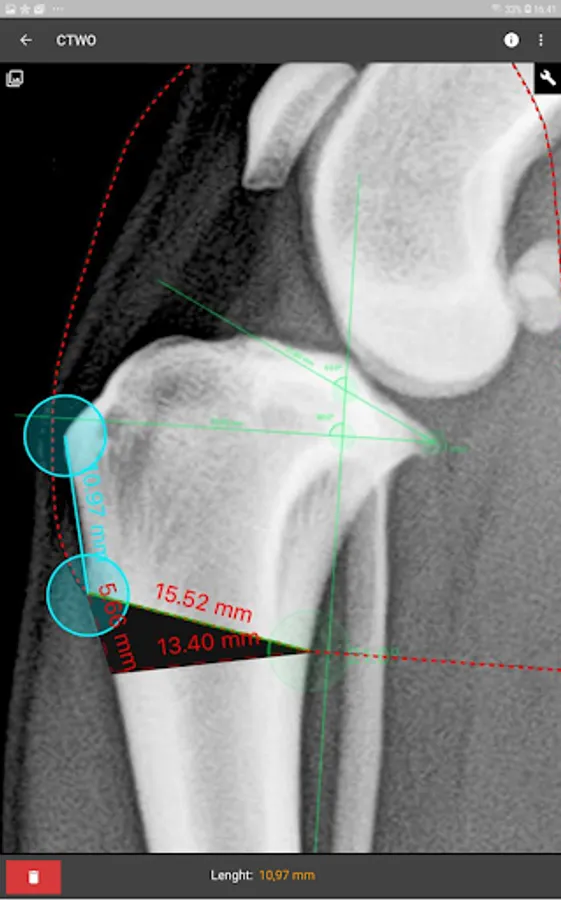

a) Linear Measure.

b) Radial measure/Circle draw.

c) Angle measure/Triangle draw.